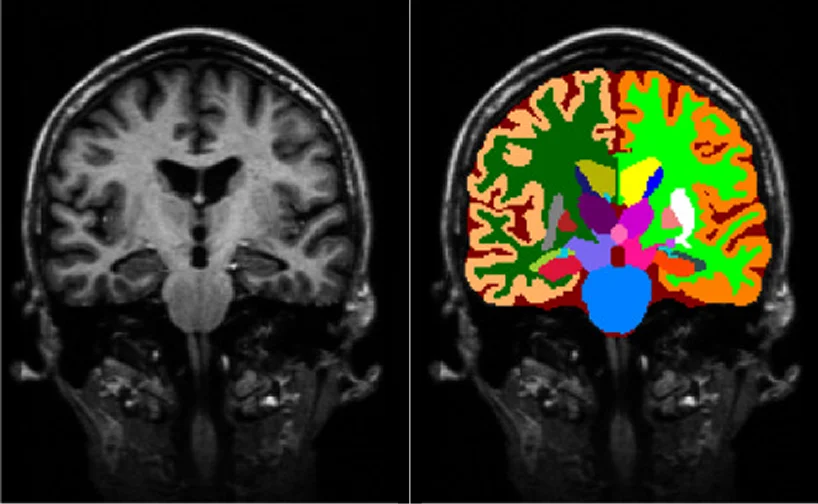

Medical image segmentation is the process of partitioning MRI scans into meaningful regions—such as brain structures, lesions, or tissue classes.

Accurate segmentation enables:

Without reliable segmentation, even the most advanced AI architectures fail to deliver clinical value.